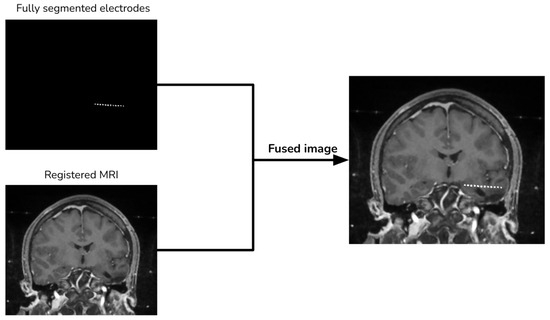

2.4. Image Merging

Finally, we add the segmented electrodes to the aligned MRI to produce the fused image (Figure 6).

Figure 6. Image merging procedure.

Diagnostics 13 03420 g006